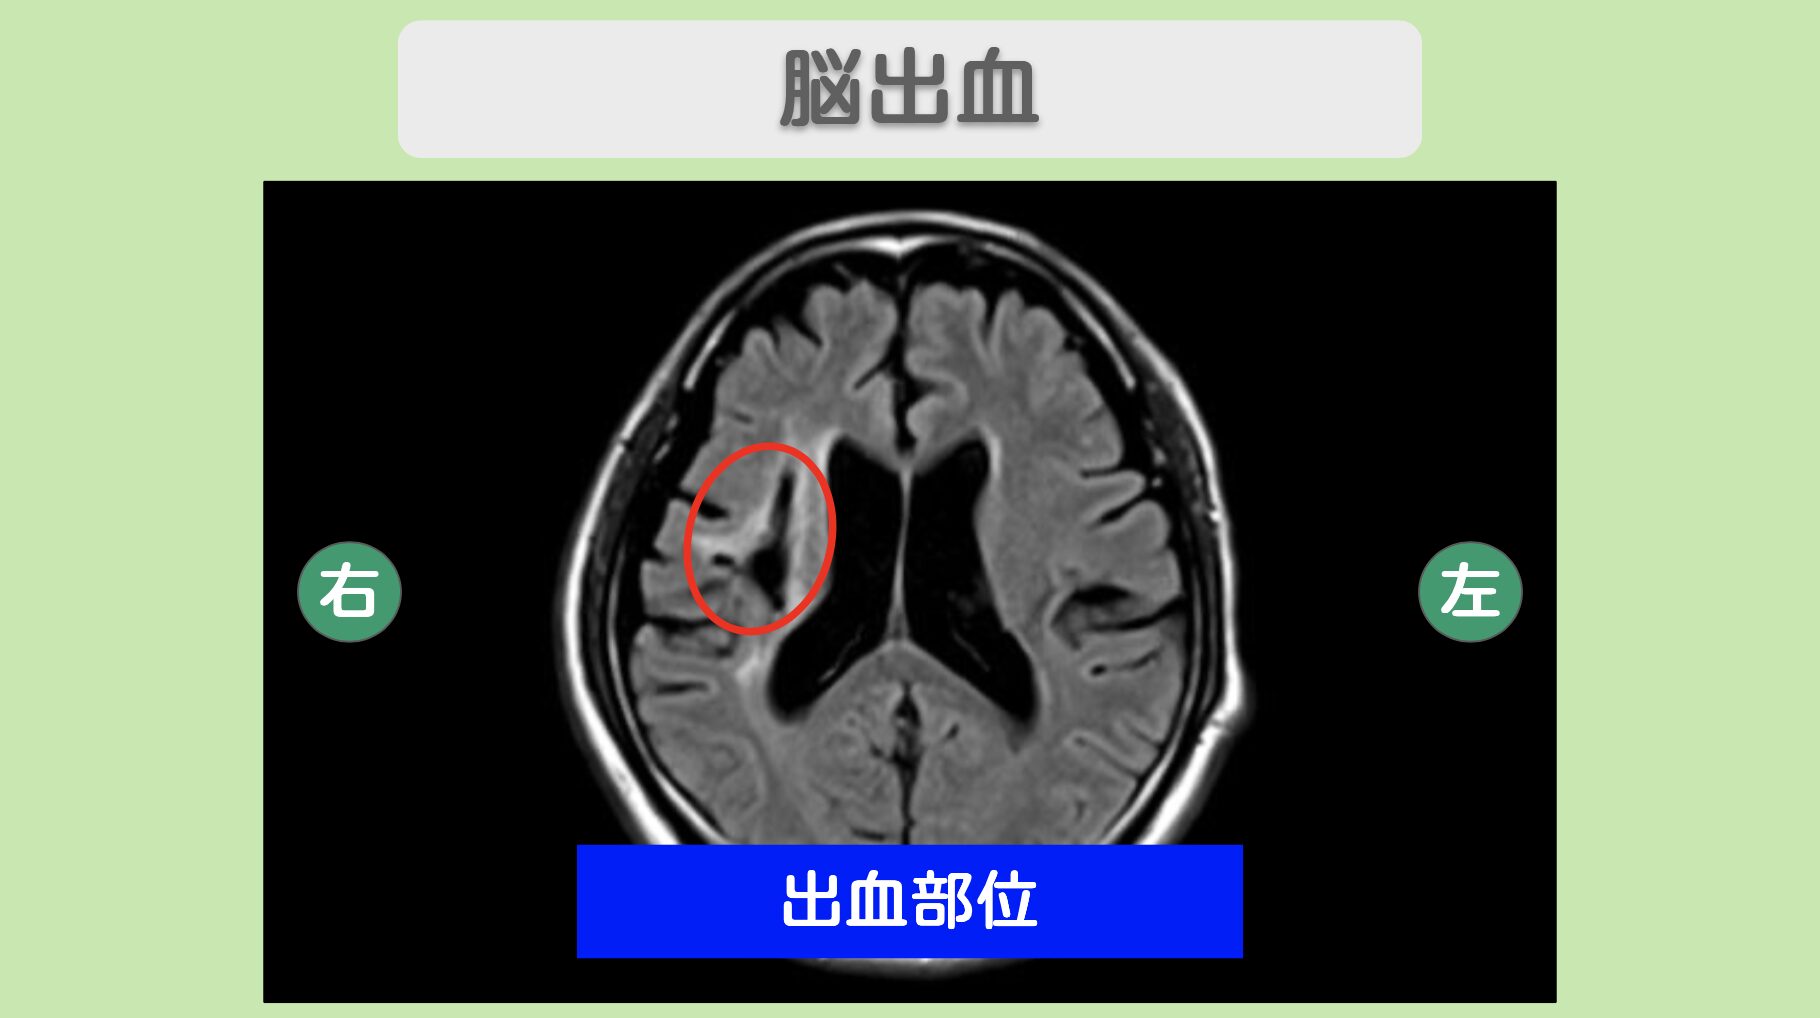

MRI 所見

<治療内容>2億個の”リペア幹細胞”を計3回点滴投与

2億個の“リペア幹細胞”を計3回にわたり点滴で投与しました。手術や入院の必要はなく、身体への負担を抑えながら治療を進めることができました。